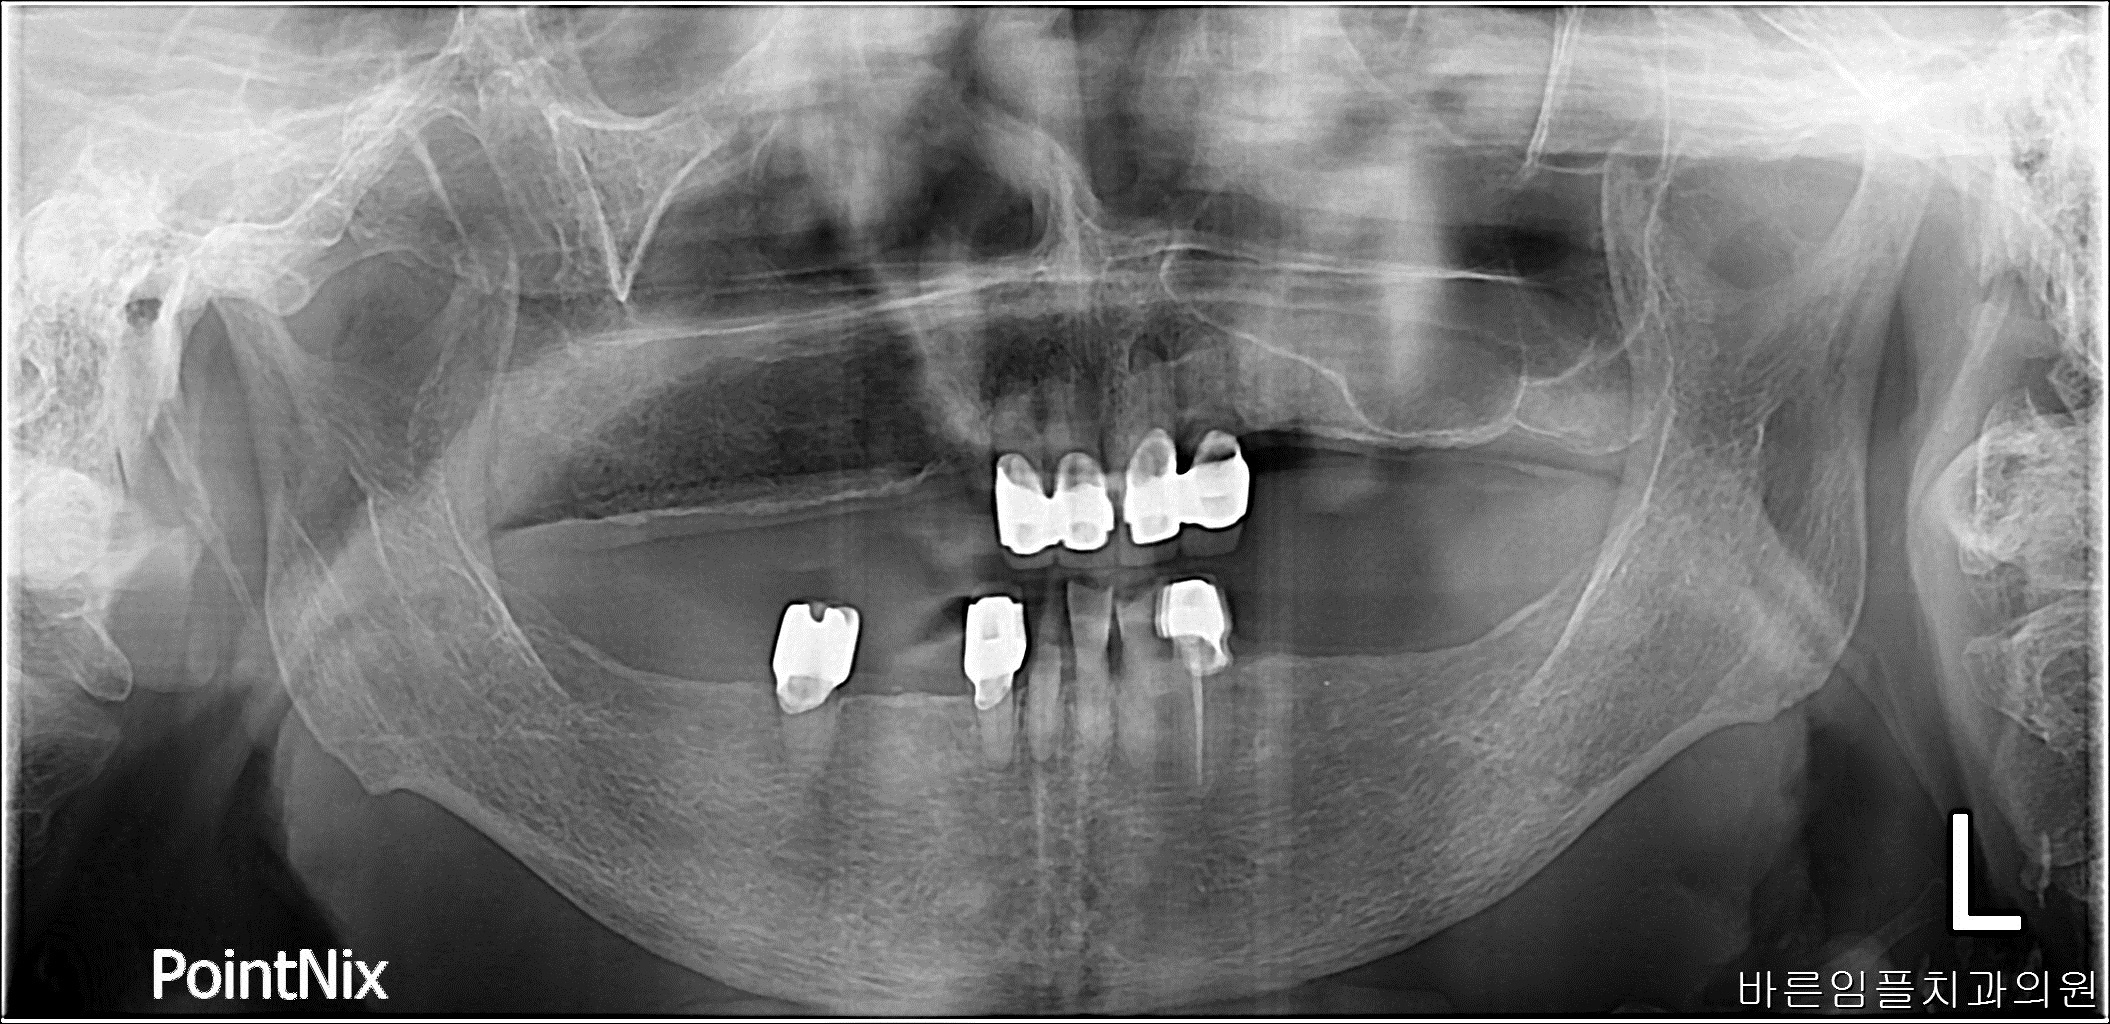

이ㅇㅇ / 수면임플란트 페이지 정보 작성일 23-10-27 17:03 2023-03-02 이ㅇㅇ Before 2023-08-05 이ㅇㅇ After 이ㅇㅇ / 수면임플란트 목록 이전글차ㅇㅇ / 수면임플란트 다음글 박ㅇㅇ / 수면임플란트